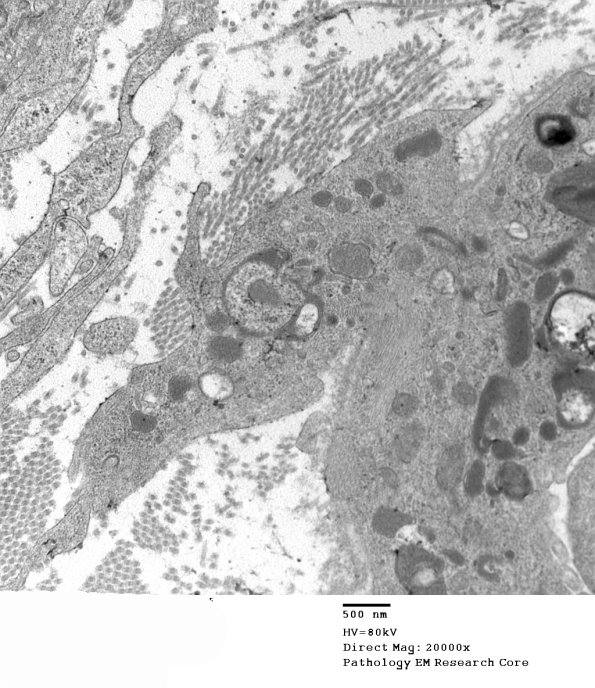

The axon is already demyelinated by the macrophage within the Schwann cell sheath which has two parts, one of which is in the endoneurial space. (electron micrograph)